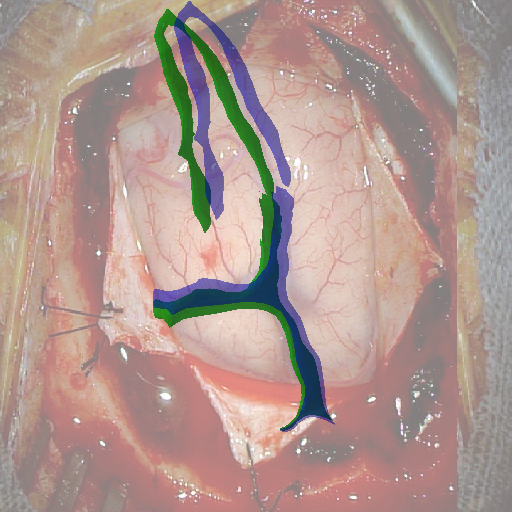

We tested our method retrospectively on 6 clinical datasets from 6 patients (cases) (see Fig. 5). These consisted of preoperative T1 contrast MRI scans and intraoperative images of the brain surface after dura opening. Cortical vessels around the tumors were segmented and triangulated to generate 3D meshes using 3D Slicer. We generated 100 poses for each 3D mesh (i.e.: each case) and used a total of 15 unique textures from human brain surfaces (different from our 6 clinical datasets) for synthesis using . In order to account for potential intraoperative brain deformations [4] we augment the textured projection with elastic deformation [21] resulting in approximately 1500 images per case. The surgical images of the brain (left image of the stereoscopic camera) were acquired with a Carl Zeiss surgical microscope. The ground-truth poses were obtained by manually aligning the 3D meshes on their corresponding images.

Test and Comparison on Clinical Images

We compared our method (Ours) with segmentation-based methods (ProbSEG) and (BinSEG) [7]. These methods use learning-based models to extract binary images and probability maps of cortical vessels to drive the registration. We report in Tab. 1 the distances between the ground truth and estimated poses. Our method outperformed ProbSEG and BinSEG with an average ADD error of mm compared to mm and mm, respectively. Our errors remain below clinically measured neuronavigation errors reported in [4], in which a mm average initial registration error was measured in 15 craniotomy cases using intraoperative ultrasound. Our method outperformed ProbSEG in 5 cases out of 6 and BinSEG in all cases and remained within the clinically measured errors without the need to segment cortical vessels or select landmarks from the intraoperative image. Our method also showed fast intraoperative computation times. It required an average of only milliseconds to predict the pose (tested on research code on a laptop with NVidia GeForce GTX 1070 8GB without any specific optimization), suggesting a potential use for real-time temporal tracking.

Fig. 5 shows our results as Augmented Reality views with bounding boxes and overlaid meshes. Our method produced visually consistent alignments for all 6 clinical cases without the need for initial registration. Because our current method does not account for brain-shift deformation, our method produced some misalignment errors. However, in all cases, our predictions are similar to the ground truth.